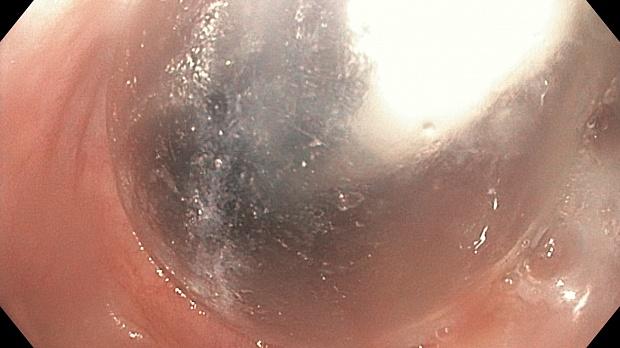

При осмотре признаки ахалазии кардии 3-й степени по Гаджелло: значительное расширение просвета пищевода в н/3, наличие большого количества остатков пищи и слизи, просвет пищевода имеет извитой ход, слизистая в кардии бледная и утолщена,  ПЖП открывается на 0,3 см при длительной инсффляции.